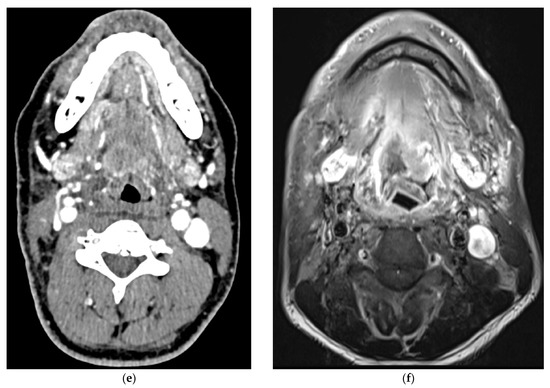

5. Imaging of Oropharyngeal Cancers

8.1. Initial Staging

8.2. Response Assessment